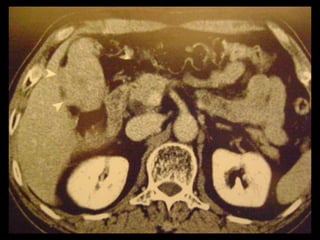

Achados na TC: cálculos biliares, espessamento da

parede, alterações inflamatórias

perivesiculares, bile com alta

atenuação, borramento da interface VB-fígado e

aumento transitório da atenuação do fígado

perivesicular;

Colecistite aguda US é a modalidade de imagem de escolha; Em geral, a TC é realizada para avaliar pacientes com suspeita de complicações do quadro de colecistite aguda, como perfuração por exemplo. Achados na TC: cálculos biliares, espessamento da parede, alterações inflamatórias perivesiculares, bile com alta atenuação, borramento da interface VB-fígado e aumento transitório da atenuação do fígado perivesicular;